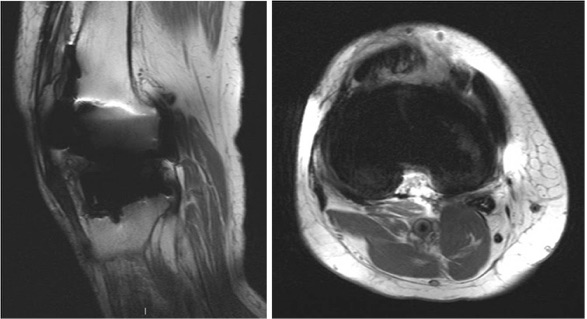

Evaluación con resonancia magnética de artroplastias totales de rodilla sintomáticas. [MRI evaluation of symptomatic total knee arthroplasties ].